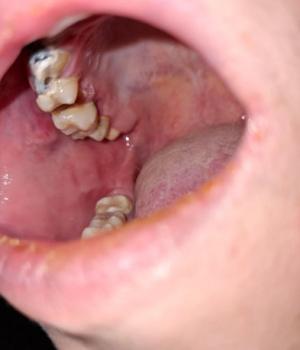

Severe Broken and Infected Teeth Case Analysis With Low-Cost Treatment Options

1. Visual Findings (Deep Examination)

Severely broken teeth:

One or more teeth appear fractured down to the root level.

Loss of crown structure with dark, necrotic tissue visible.

Advanced decay:

Extensive caries involving dentin and likely the pulp.

Appearance consistent with root caries and long-standing infection.

Soft tissue condition:

Surrounding gums appear inflamed.

Possible presence of chronic dental infection or abscess tract.

Overall condition:

Indicates multiple untreated dental problems, likely progressive over months or years.